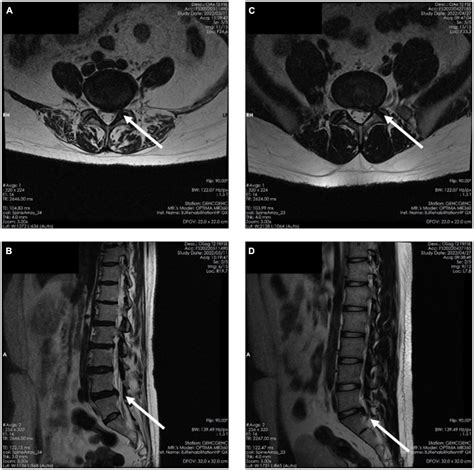

• Imaging Tests: X-rays, MRI, or CT scans can provide detailed images of the spine, helping to identify any abnormalities or damage to the L5 S1 disc.